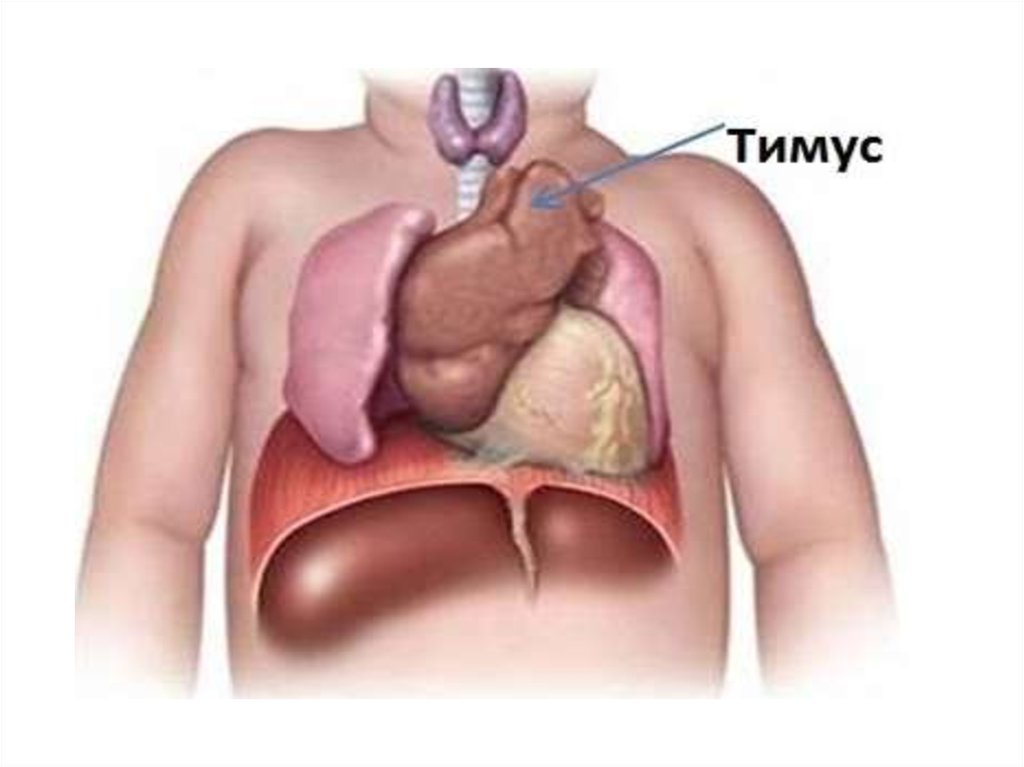

Тимомегалия: что это такое и как проявляется